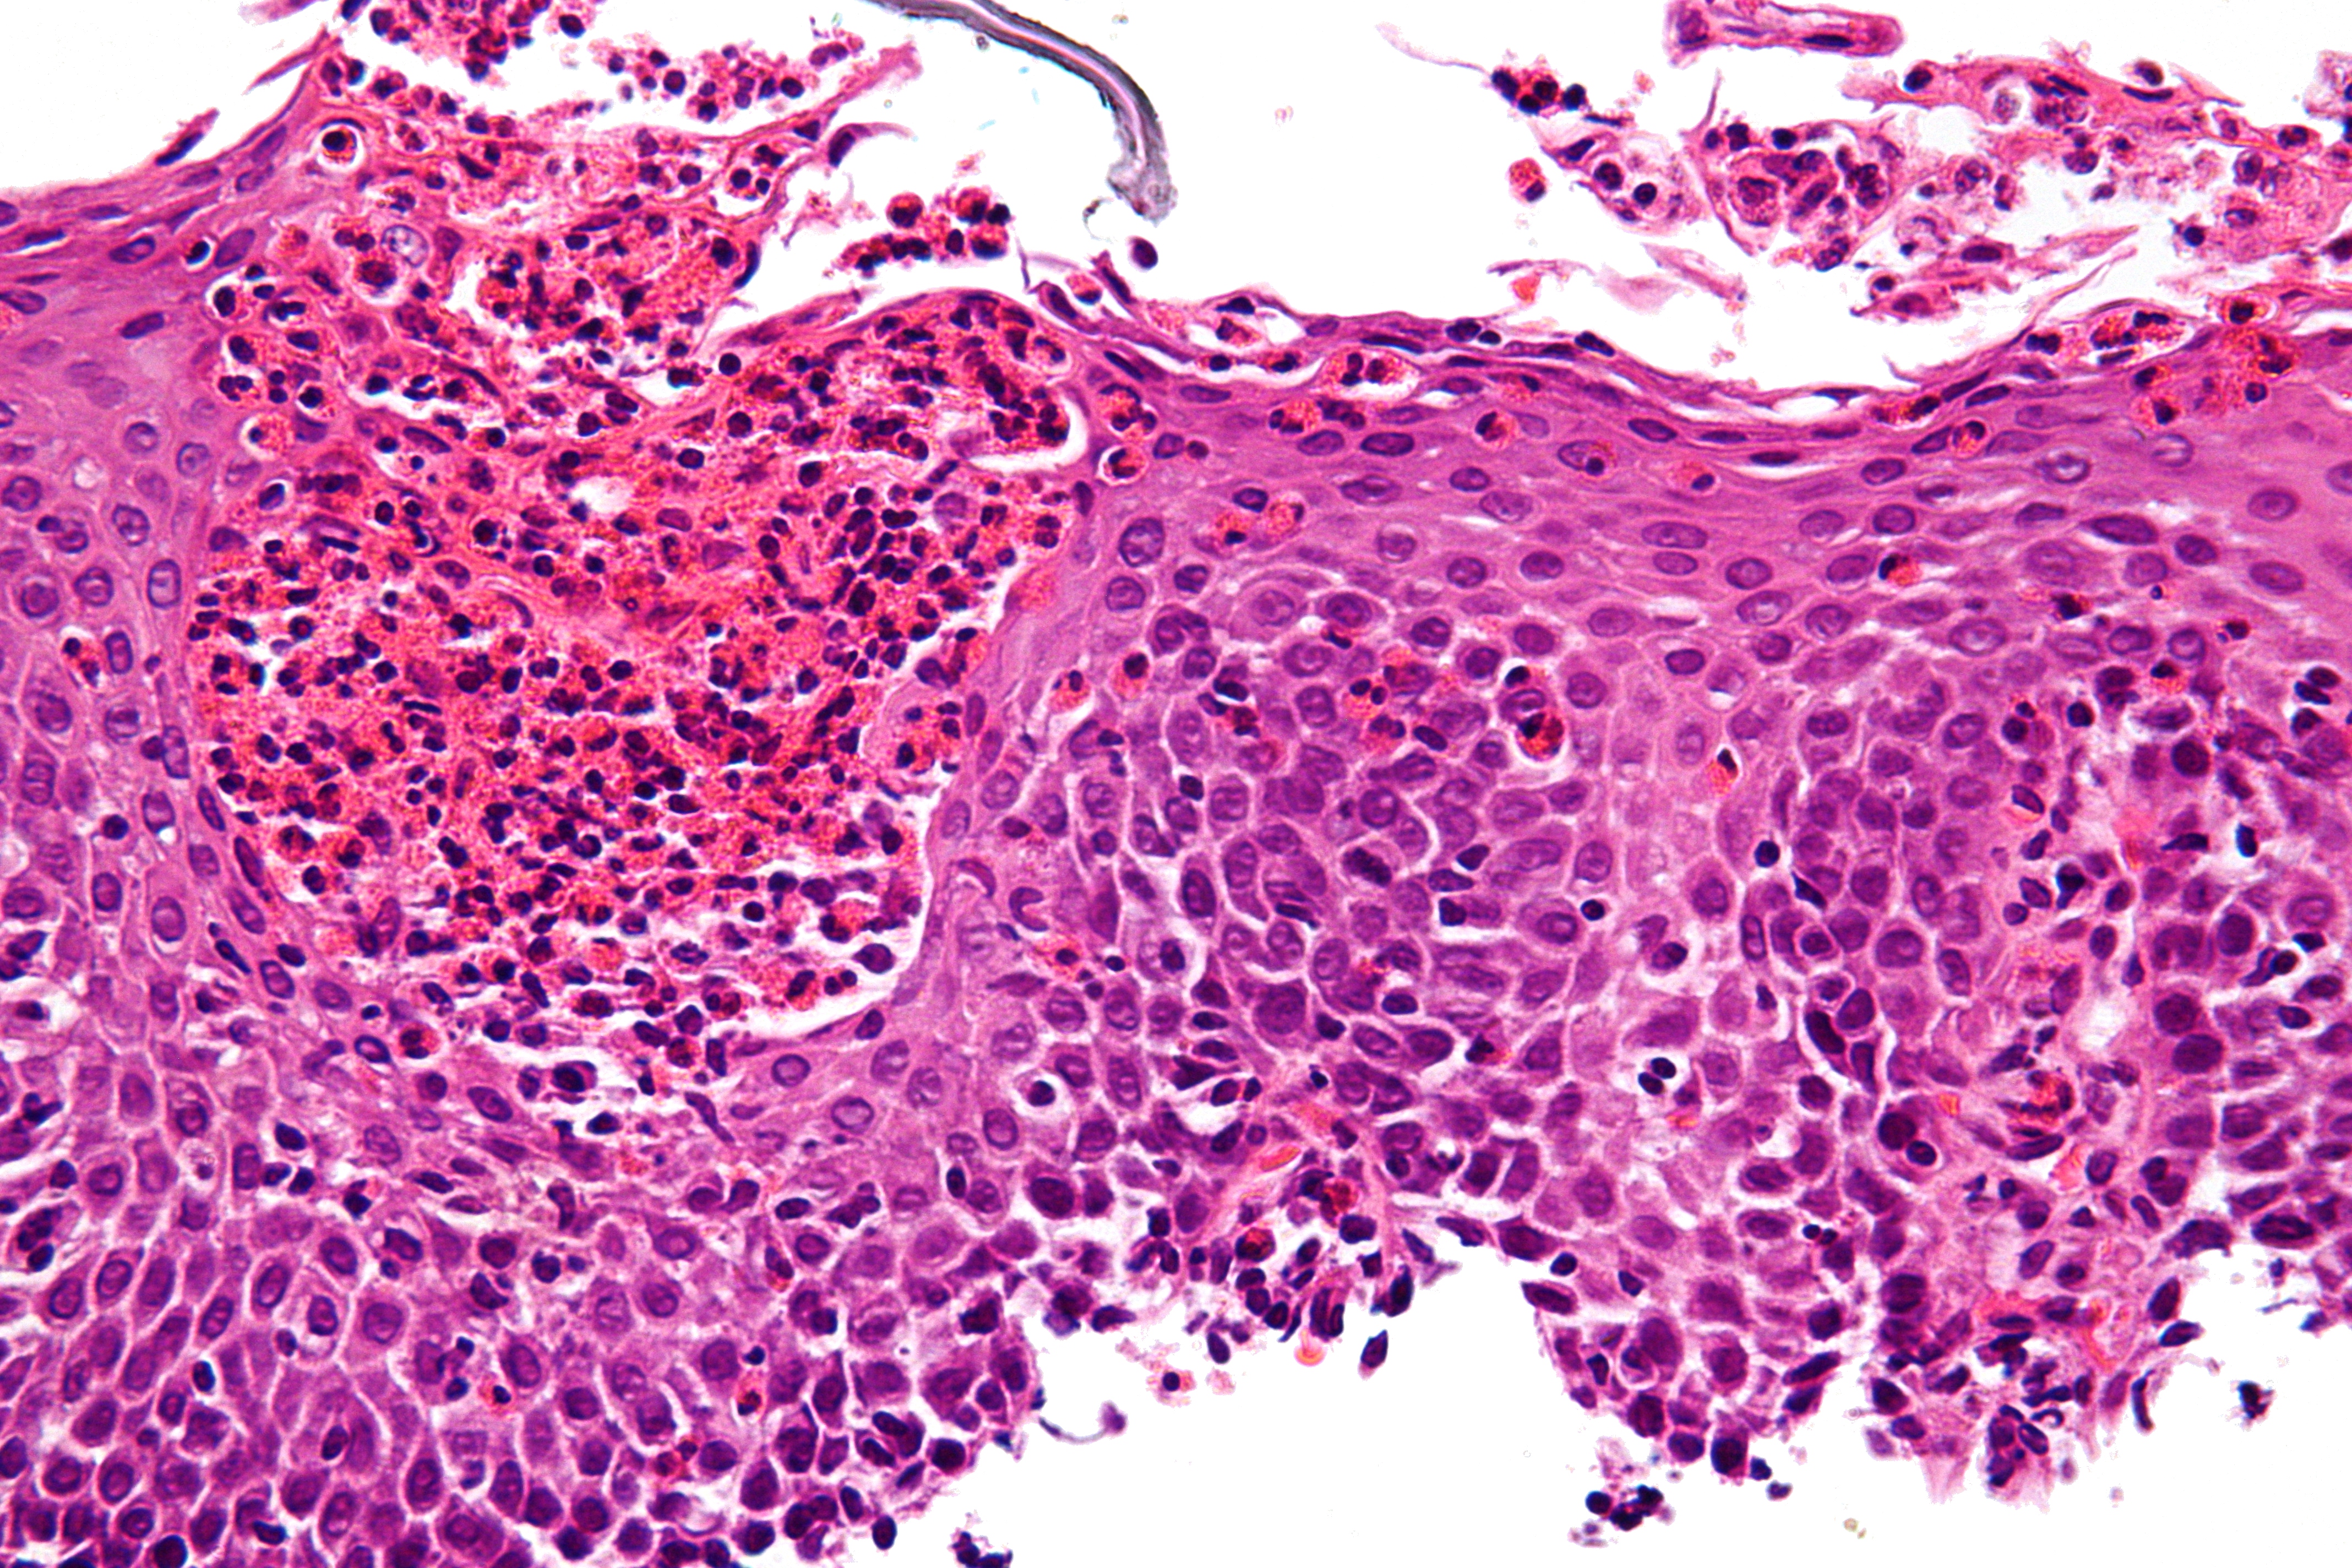

감염성 식도염은 바이러스, 곰팡이, 기생충 또는 세균 감염으로 인해 발생하며, 면역 결핍이 있는 사람에게 더 자주 발생한다. 감염성 식도염의 유형은 다음과 같다.- 곰팡이: 칸디다 (식도 칸디다증)

내시경을 통해 이러한 감염성 식도염들을 구별할 수 있다.[12]

호산구 식도염은 식도 내 호산구 농도가 높아서 발생한다. 식도 내 호산구의 존재는 알레르겐에 의한 것일 수 있으며 종종 위식도 역류 질환과 관련이 있다. 염증과 산 역류 사이의 인과 관계는 제대로 확립되지 않았으며, 최근 연구(2016년)에서는 역류가 염증을 유발하지 않는다는 것을 시사하고 있다.[6] 이 식도염은 음식 또는 흡입된 알레르겐에 대한 알레르기에 의해 유발될 수 있다. 이 유형은 여전히 잘 알려져 있지 않다.

식도염은 상부 내시경 검사, 생체 검사, 상부 위장관 조영술(또는 바륨 연하 검사) 및 실험실 검사를 통해 진단할 수 있다.[4]

상부 내시경 검사는 내시경을 사용하여 식도를 관찰하는 시술이다. 식도를 관찰하는 동안 의사는 작은 생체 검사를 채취할 수 있다. 생체 검사는 식도 염증을 확인하는 데 사용될 수 있다.

식도에서 채취한 생체 검사에서 실험실 검사를 수행하여 식도염의 원인을 파악하는 데 도움을 줄 수 있다. 실험실 검사는 곰팡이, 바이러스 또는 세균 감염을 진단하는 데 도움이 될 수 있다. 백혈구 검사는 호산구 식도염을 진단하는 데 도움이 될 수 있다.